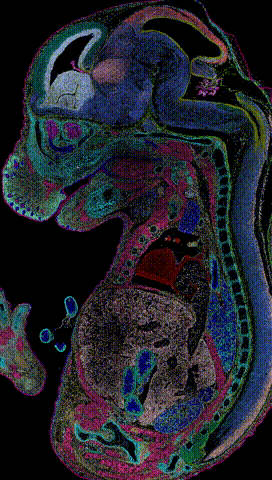

華大時(shí)空組學(xué)技術(shù)目前在全球處于領(lǐng)先地位,可以從時(shí)間和空間維度研究細(xì)胞及分子在組織中的定位和功能,將認(rèn)識(shí)生命空間的分辨率提高到了500納米的亞細(xì)胞層級(jí),視野最大可達(dá)13厘米x13厘米,被譽(yù)為“超廣角百億像素生命照相機(jī)”。

目前,華大時(shí)空組學(xué)技術(shù)已助力國(guó)內(nèi)外科研團(tuán)隊(duì)取得一系列突破性成果。2022年5月,Cell出版社官網(wǎng)以專題的形式發(fā)布了全球首批生命時(shí)空?qǐng)D譜。其中,小鼠胚胎發(fā)育時(shí)空?qǐng)D譜以封面文章形式在Cell發(fā)表。這是人類首次從時(shí)間和空間維度上,對(duì)生命發(fā)育過(guò)程中的基因和細(xì)胞變化過(guò)程進(jìn)行超高精度解析。